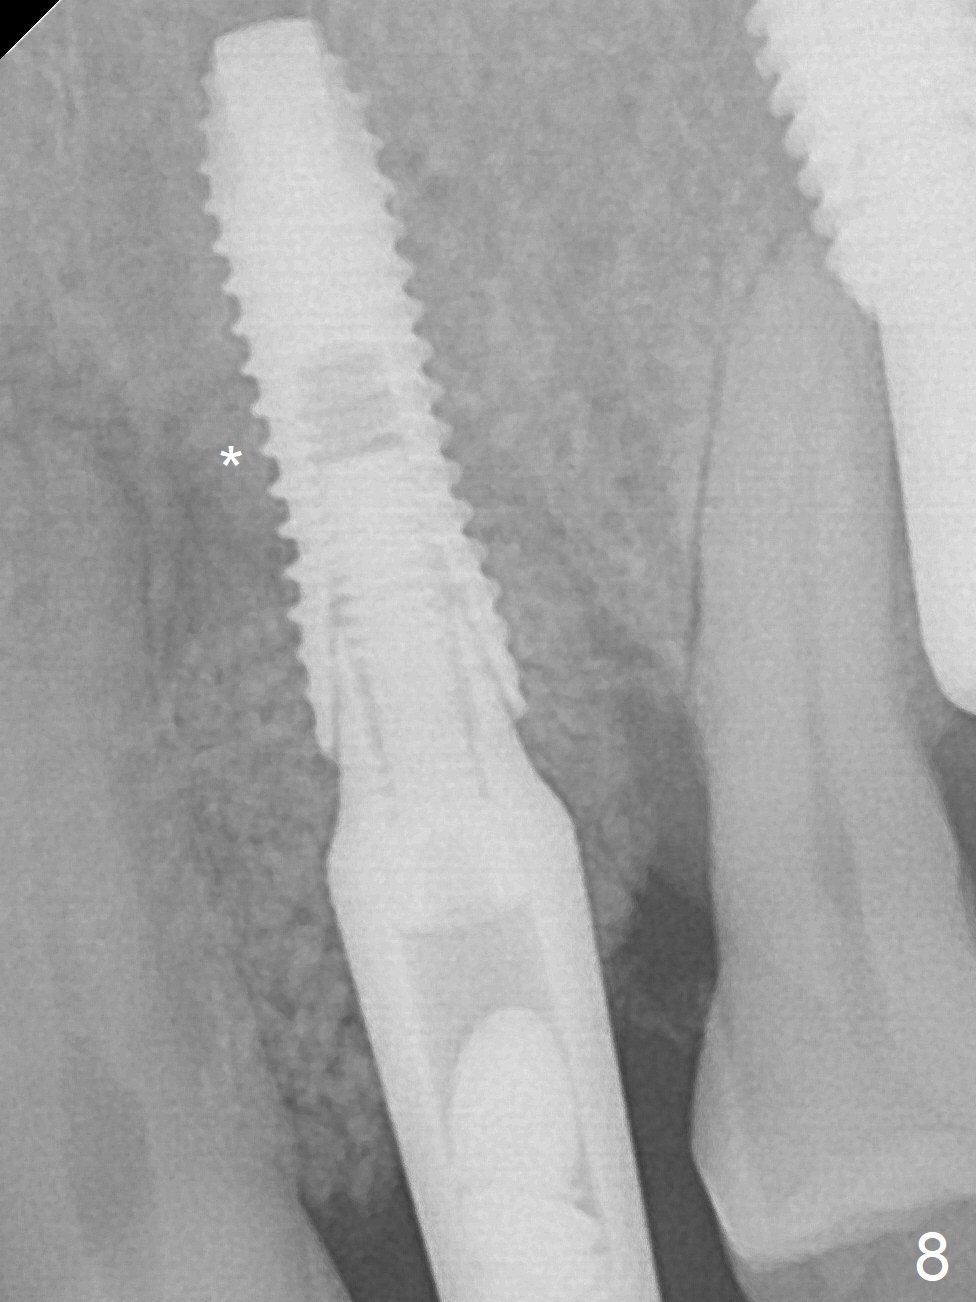

A few days prior to surgery, the tooth #12 developed abscess, self controlled by water pik (Fig.1 *). The buccal plate is defective. Initial osteotomy is close to the root of the tooth #11 (Fig.2). After adjustment of the trajectory and the depth of osteotomy (Fig.3), a 3.8x15 mm dummy implant is placed (Fig.4,5). In spite of a shorter implant (3.8x13 mm) placed deeper, approximately 7 mm implant threads are not covered buccally by the native bone (Fig.6 red dashed line). If the implant were placed deeper, the crown/implant ratio would become more unfavorable (abutment screw loosening, Fig.7). Since a mill abutment (4.5(2) mm) is inserted before Vanilla Graft, the deepest portion of the socket is unfilled (Fig.7 *). With meticulous use of a long explorer and additional allograft, the space is closed (Fig.8 *). The buccal plate collapses with apparently fistula formation 2 months postop. The patient removes the provisional for cleaning. It appears that the mill abutment is buccally placed and needs heavy reduction. The mill abutment is loose 2 months 10 days postop. When it is retightened, it tilts distal. Bone remains around the implant 6 months postop (Fig.9). Without a provisional at #12 for 5 months, the tooth #13 appears to have been shifted mesially (Fig.10 arrow). The mill abutment at #12 changes to a healing one. A lingual button is placed in the mesial surface of #13. Splinted provisional is fabricated with supraocclusion at #14 and 15 as an anchor (implants). The tooth #13 is being distalized with power chains. Limited ortho is finished nearly 2 months post banding (Fig.15,16).